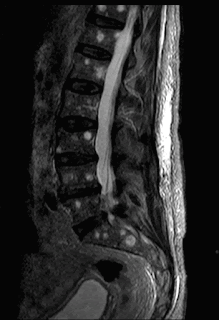

Το ποσοστό της παραπομπής για μαγνητική τομογραφία, ασθενών με οσφυαλγία, στις Ηνωμένες Πολιτείες αυξάνεται με ανησυχητικό ρυθμό, παρά τις ενδείξεις ότι αυτό δεν συνοδεύεται με τη βελτίωση της υγείας των ασθενών. Η υπερβολική αυτή ζήτηση σε απεικονιστικές εξετάσεις της οσφυϊκής μοίρας της Σ.Σ., σε άτομα με οσφυαλγία συσχετίζεται με, και είναι πιθανό να συμβάλλει, σε μια αύξηση των χειρουργικών επεμβάσεων (ακόμη και 2-3 φορές περισσότερες), κατά τα τελευταία 10 χρόνια.

Επιπλέον, η γνώση του ασθενούς για τις απεικονιστικές ανωμαλίες, μπορεί να μειώσει πραγματικά την αυτο-αντίληψη για το πρόβλημά του και μπορεί να οδηγήσει σε κινησιοφοβία, αλλά και καταστροφικές συμπεριφορές, που μπορεί να προδιαθέτουν για την χρονιότητα του προβλήματος.